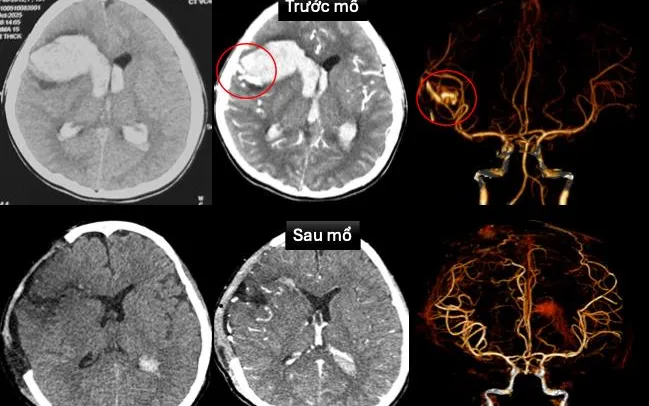

Tại Bệnh viện Nhi đồng 1, bệnh nhi được cấp cứu tích cực, siêu âm tim và chụp cắt lớp vi tính sọ não dựng hình mạch máu. Kết quả cho thấy dị dạng động tĩnh mạch trán phải vỡ, gây xuất huyết não lan vào não thất trên nền bệnh cơ tim xốp, một bệnh lý tim mạch bẩm sinh hiếm gặp.

Bệnh viện đã huy động hội chẩn khẩn liên chuyên khoa. Bác sĩ tim mạch can thiệp đặt máy tạo nhịp tạm thời, trong khi ekip ngoại thần kinh phẫu thuật cấp cứu mở sọ giải áp, vi phẫu cắt dị dạng mạch máu và lấy máu tụ. Sau mổ, bệnh nhi được điều trị hồi sức tích cực, chống phù não, duy trì thông khí và thuốc vận mạch.

Nhờ xử trí kịp thời, bệnh nhi dần tỉnh táo, vận động yếu nhẹ chân phải, tim mạch ổn định, đã rút máy tạo nhịp và ngưng thuốc vận mạch. Hình ảnh kiểm tra sau mổ cho thấy không còn dị dạng mạch máu, chức năng tim cải thiện rõ.